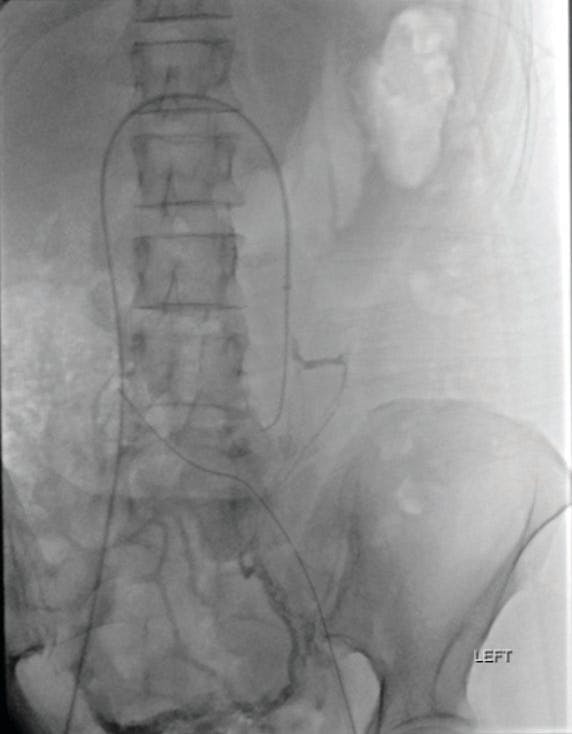

The patient underwent left ovarian vein embolization using Ruby® Coils (Penumbra, Inc.), with complete resolution of her left-sided pelvic pain. However, at follow-up, she reported persistent, moderate right-sided pain. Given dilation of the right ovarian vein on her original imaging (Figure 1), she was brought back for diagnostic venography and subsequent right ovarian vein embolization. It is important to note that the dilated right ovarian vein is less likely to show reflux on CT imaging, even when venous timed. In this case, the right ovarian vein did light up on CT (Figure 2) but much less so when compared with the left ovarian vein.

Figure 1. Preoperative image from before the second procedure showing large dilated right ovarian vein (arrow).

Figure 2. Initial venogram of very large, dilated right ovarian vein.